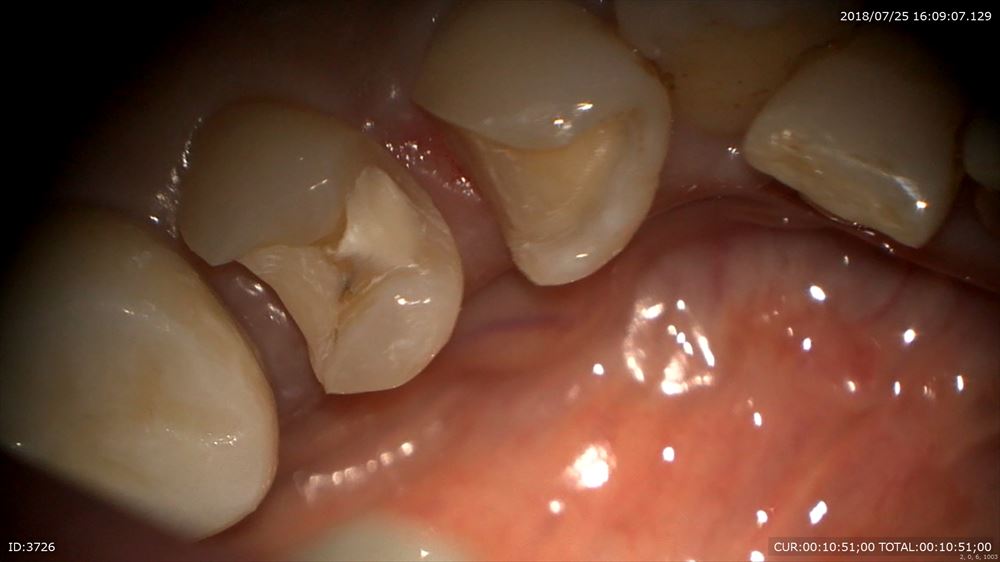

歯科ドックで左下の根管治療の不備とその手前に通常のレントゲンには映りにくい場所の虫歯をCTで発見しました。

ここに肉眼では虫歯があるなんて思いませんよね。

ほらCTとマイクロスコープを使用すると。。

CTにはしっかり写っていました。歯科ドックは大切。

神経に触れています。